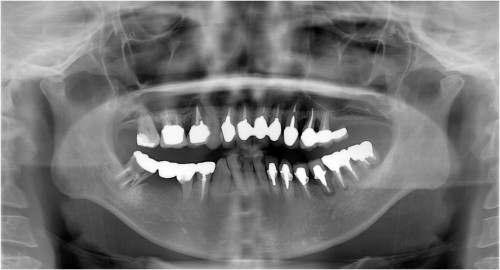

杉山1 初診時 ◎